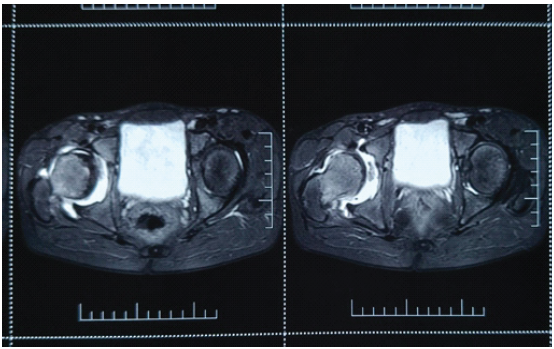

Hip disorders in the paediatric population (patients <16 years) represent a varied collection of conditions ranging from traumatic, developmental, infectious, neoplastic, and metabolic causes [1]. These pathologies, if not promptly diagnosed and treated, frequently result in long-term morbidity, including permanent deformities, chronic pain, gait abnormalities, and compromised quality of life in adulthood [1,2]. The unique developmental anatomy of the pediatric hip, characterized by the presence of a vulnerable physeal plate and changing vascular patterns, contributes to its susceptibility to specific age-related diseases [3]. Common non-traumatic paediatric hip disorders include developmental dysplasia of the hip (DDH) (Fig. 1), Legg-Calvé-Perthes disease (Perthes’) (Fig. 2 and 3), slipped capital femoral epiphysis (SCFE) (Fig. 4), and infective conditions such as septic arthritis (Fig. 5) and tubercular arthritis [3].

Figure 3: Magnetic resonance imaging image of Perthes disease right hip showing femoral head irregularities, cystic changes, hyperintense lesion in femoral head.